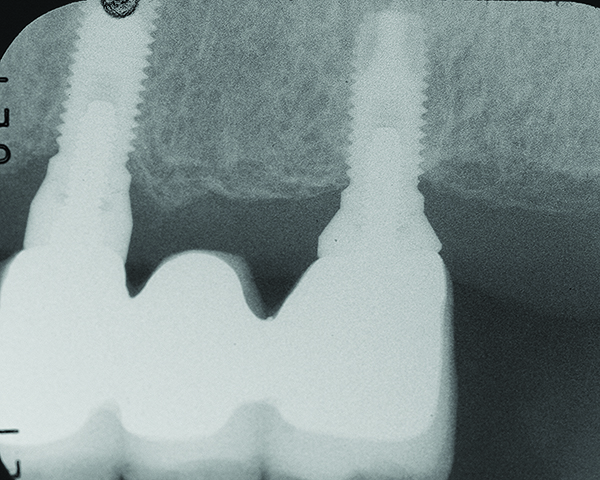

Fig 7 through Fig 14. Periapical radiographs of a 62-year-old woman who received a fixed porcelain-fused-to-metal reconstruction supported by abutments by internally connected dental implants. Fig 7 through Fig 10 are at initial prosthesis placement: mandibular site Nos. 30 and 29 (Fig 7); mandibular site Nos. 26, 25, and 23 (Fig 8); mandibular site Nos. 23 and 21 (Fig 9); mandibular site Nos. 21 through 19 (Fig 10). Fig 11 through Fig 14 are 11 years later (2013) and show excellent preservation of the vertical bone levels around the implants: mandibular site Nos. 30 and 29 (Fig 11); mandibular site Nos. 26 and 25 (Fig 12); mandibular site Nos. 25 and 23 (Fig 13); mandibular site Nos. 20 and 19 (Fig 14). It is interesting to note that in the mandibular right posterior quadrant there is a matched pair, ie, an external hex dental implant (No. 30) adjacent to an internally connected dental implant (No. 29). The bone levels around each of these designs are well-preserved at the 11-year follow-up.